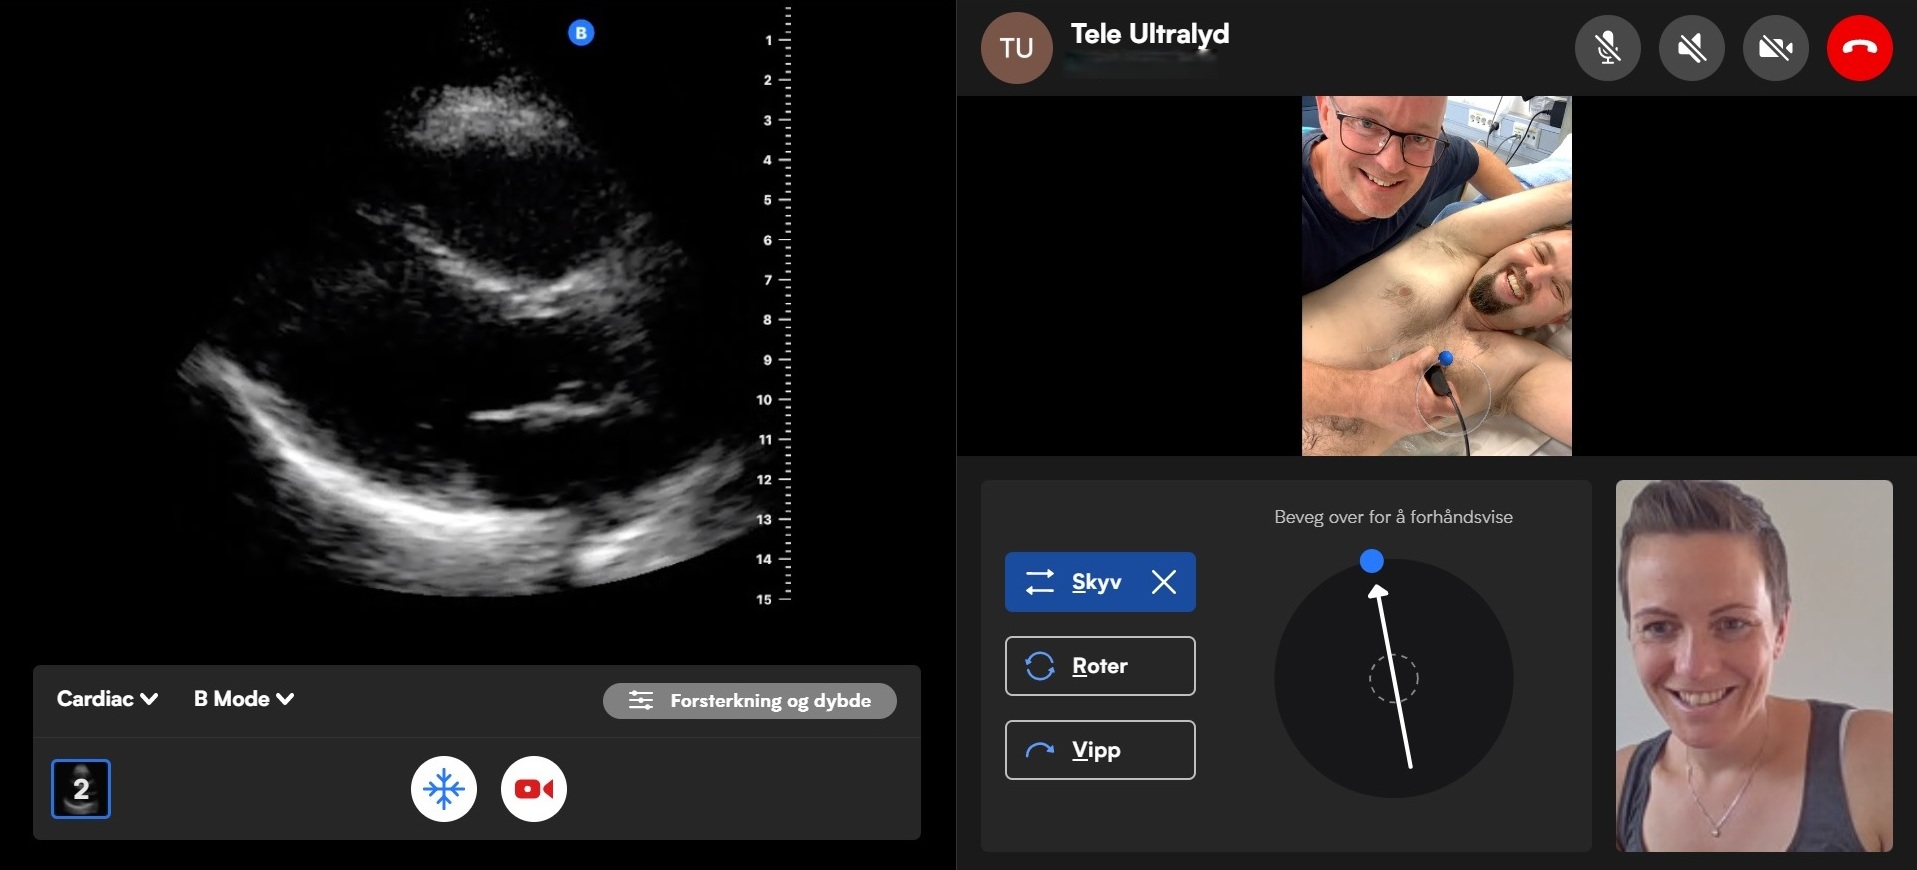

For første gang kan livreddende ultralydundersøkelser utføres i Nordsjøen. Undersøkelsene skjer i samarbeid med spesialist på land fra Universitetet i Stavanger. Løsningen gir nye måter å bruke ressursene i helsetjenesten – både nasjonalt og internasjonalt.

Hittil har det ikke vært mulig å få gjennomført ultralydundersøkelser eller annen medisinsk bildediagnostikk på installasjonene i Nordsjøen. Pasienter som har blitt syke på kontinentalsokkelen har derfor måttet bli transportert til land for å bli undersøkt.

I mange tilfeller vil rask avklaring ved hjelp av ultralydundersøkelser gjøre at behandling kan startes på skadestedet eller på vei til sykehuset, i stedet for ved ankomst. Det vil både kunne spare liv og redusere komplikasjoner og lidelse hos pasientene.

Ultralyd har de siste tiårene gått fra å være et verktøy for legespesialiteter til å bli et viktig verktøy i store deler av helsetjenesten. Med dagens bærbare ultralydapparater kan undersøkelser gjøres hjemme hos pasienter, på skadestedet, i ambulansen, i helikopter, i akuttmottak eller på hospitaler offshore.

Systematisk bruk av ultralyd offshore gir raskere vurderinger og bedre grunnlag for å avgjøre om pasienten kan behandles på stedet eller må evakueres.

Prisen bygger på forskningen til doktorgradsstudent Victoria Vatsvåg. Den viser hvordan kompetanseheving og fjernveiledning i ultralyd gir helsepersonell bedre beslutningsstøtte når hjelpen er langt unna.

En stor utfordring er at for få har nødvendig kompetanse til å gjennomføre ultralydundersøkelser. Prosjektet inneholder derfor også en utdanningsdel. Her får nye grupper helsepersonell, som paramedisinere og sykepleiere som ikke tidligere har vært inkludert i ultralyddiagnostikk, opplæring i verktøyet.